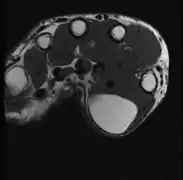

A physical exam is typically the easiest way to diagnose it. Rarely, a tissue biopsy or imaging may be required. The imaging modality of choice is magnetic resonance imaging (MRI) because it has superior sensitivity of distinguishing it from liposarcoma as well as mapping the surrounding anatomy.[22]

MRI showing lipoma of the arm